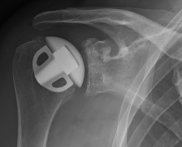

Abbildung2Abbildung1

left: X-ray image of an omarthrosis

right: X-ray of a healthy shoulder joint

X-rays can be used to reliably diagnose the extent of joint wear. In the case of severe osteoarthritis, for example, the joint space and the formation of jagged edges (osteophytes) can be detected. If additional damage to the tendons of the shoulder (rotator cuff) is suspected, ultrasound examination (sonography) or magnetic resonance imaging (MRI) can help clarify the situation.